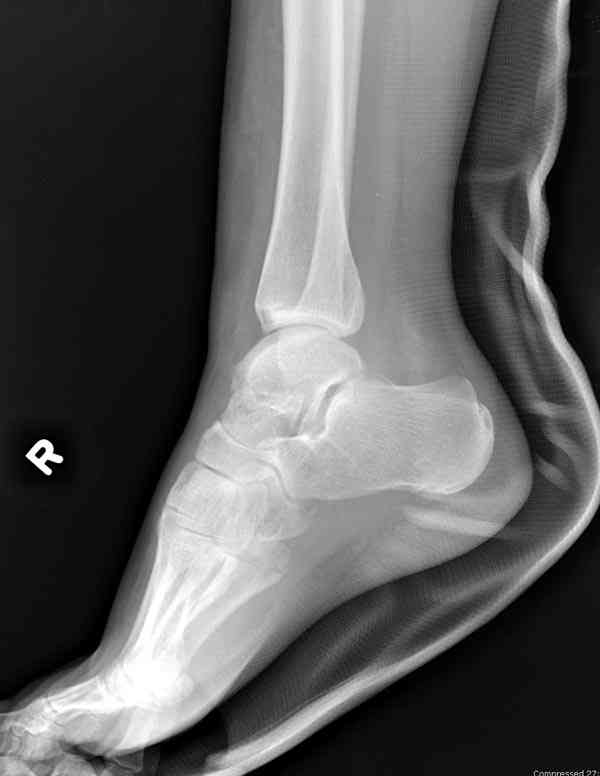

Interesting case

The ankle joint looks ruined. I wonder howcome is it as ruined after 2 days. I would open the joint( Some people would artroscope it) and judge the osteosynthes vs ankle fusion according to the ankle joint condition. The subtalar does not look injured, but if you feel there is a clinical

problem- CT it. Above all- when I see such an X-Ray I call the resident who ordered it and tell him that I would expect him first thing to reduce it on arrival since the soft tissue suffer and I hope that currently the p-nt is reduced to some extent at least.

Sorry- I revised it and the talus is fractured- take him to the theater at once and reduse it with Int Fix

The soft tissue will be a problem- Ex Fix will be better thn plaster

а основании двух видов ренгенограмм невозможно радикально решить о необходимости открытой репозиции или первичного артродеза.

Для оценки состояния нужны дополнительные исследования, например Canale или Broden ренгенограммы и Компьютерная томография.

При переломах тарана всегда имеется риск AVN, а классификация Hawkins поможет разобраться с предполагаемыми осложнениями.

Если в первом типе, когда перелом шейки без смещения, тогда AVN менее 10%, при втором типе когда имеется смещение и вывих тарана в субталарном сочленении меньше 40%, а при типе III когда смещение в голеностопном и субталарном суставах - около 90% и в типе IV, когда происходит полный вывих, риск AVN достигает 100%.